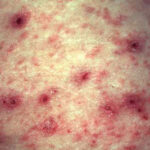

Burrows are the pathognomonic lesions of scabies and are found mostly in the florid, papulovesicular type of sarcoptic acariasis . They are produced by female mites and occur mainly on the palms and plantae, the palmar and lateral aspects of the fingers and toes, the interdigital spaces, the flexor surfaces of the wrists, the nipples of women, the genitals of men, and, to a lesser extent, on the buttocks and axillae. Characteristically, the head is spared, except in newborns and infants . The burrows appear as fine, tortuous, blackish threads a few millimeters long. A vesicle may be visible near the blind end of the burrow. The mite is situated in this vesicle and may be visible as a tiny gray speck by dermatoscopy. Although pathognomonic, the burrow is not the most common lesion seen in scabies. Small, erythematous, often excoriated papules are more frequent . |

In a third, rare variant, the so-called Norwegian scabies or crusted scabies, innumerable mites are present. Patients with this variant show widespread erythema, hyperkeratosis, crusting, nail thickening, and subungual hyperkeratosis but no obvious burrows. |